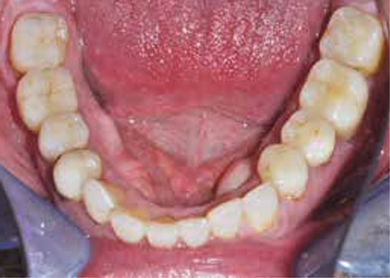

Afb. 4

Occlusaal aanzicht van de onderkaak.

Bij het extraoraal onderzoek zie ik een lichte hypertrofie van de m. masseter. Intraoraal tref ik een ernstig versleten dentitie aan waarbij de slijtage niet passend bij de leeftijd kan worden genoemd (afbeelding 2-7 en tabel 1) .